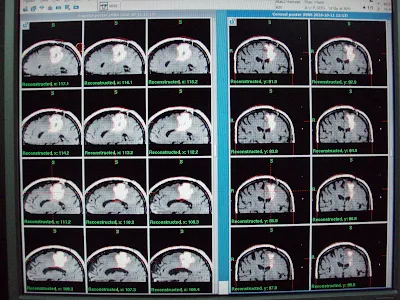

| Oligodendroglioma, Grade III (Recurrent)Before Gamma Knife |

Follow up at 4 months significant shrinkage of the tumor mass.